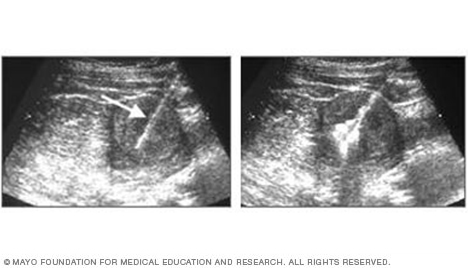

Ultrasound of needle-guided procedure

These images show how ultrasound can help guide a needle into a tumor (left), where material is injected (right) to destroy tumor cells.